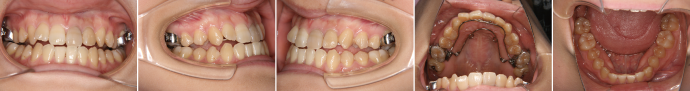

| 主訴 | 前歯の隙間が気になる |

| 年齢・性別 | 42歳 / 女性 |

| 治療方針 | 咬合力により上顎前歯が前方に傾斜したと思われるケース。元に戻りやすいため過蓋咬合をしっかり治して、保定には固定式のリテーナーも併用する。 |

| 抜歯部位 | 非抜歯 |

| 使用装置 | マルチブラケット装置 |

| 治療期間 | 16か月 |

| リテーナー | 上顎インビジブル、フィックス、下顎インビジブル |

| 費用 | 765,000円(税別) |